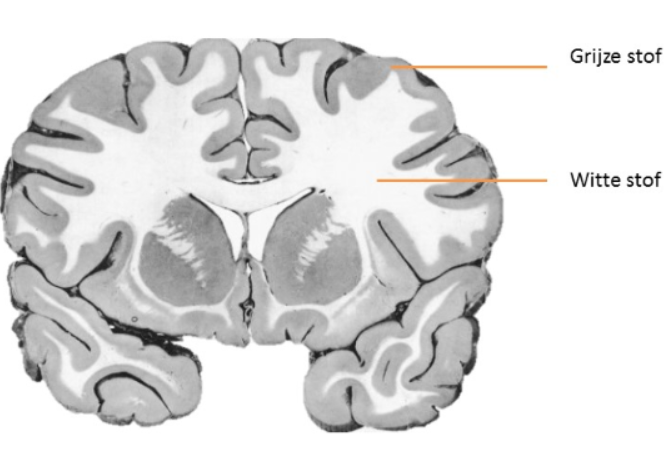

Het zenuwstelsel